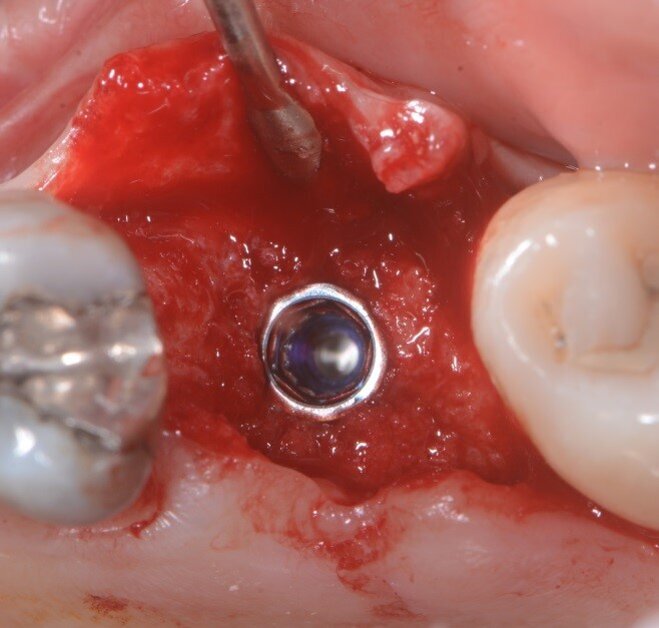

Fig. 3 -Alveolo post estrattivo.

Fig. 4 - Corticale vestibolare esposta.